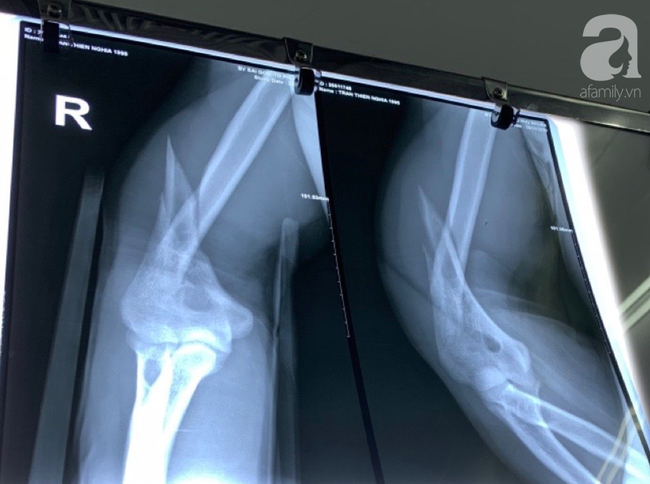

Hình ảnh X-quang sau khi kết hợp xương.

Hình ảnh X quang trước mổ cho thấy xương gãy chéo và xoắn rất không vững.